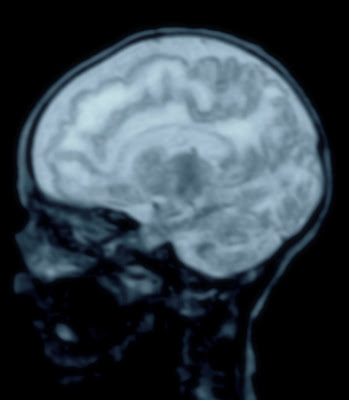

Me emociona mucho expresar mis ideas con la gente, pero sobre todo contestar preguntas o dudas que tiene la gente sobre como se hacen los estudios o que tipo de estudio hacerse ante una dolencia específica. Sin embargo el reto está en comunicar de forma coloquial y en 10 minutos todo lo relacionado con el tema seleccionado para la semana, el cual en esta semana, es la resonancia magnética. Ojalá puedan escuchar el audio y darme sus comentarios, sugerencias, marcar puntos de vista diferentes.